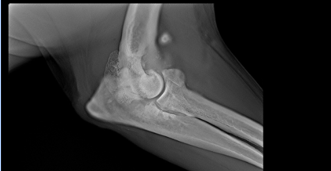

Clinical use of Adaptix - Orthopaedics

Excellent definition of bones and joints

Can be used in theatre during fracture repair